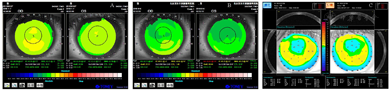

患者1,男,29岁,因双眼近视20余年于2018年1月就诊于北京美尔目润视眼科医院,要求行双眼屈光手术。既往体健,否认慢性病史。术前眼科检查:右眼眼压16.9 mmHg(1 mmHg=0.133 kPa),裸眼视力(UCVA)0.08,最佳矫正视力(BCVA)为-5.75=1.0,角膜厚度574 μm,半暗环境下瞳孔直径5.0 mm,眼底正常。左眼眼压17.6 mmHg,UCVA为0.08,BCVA为-5.00-0.50×70=1.0,角膜厚度570 μm,半暗环境下瞳孔直径5.0 mm,眼底正常。双眼角膜地形图正常,见图1A。诊断:双眼屈光不正。治疗:双眼表面麻醉下行飞秒激光小切口角膜基质透镜取出术(SMILE),术程顺利。术后第1天复查,右眼UCVA 0.5,左眼0.8;右眼BCVA为-2.25-0.75×25=1.0,左眼-0.75-0.50×25=1.0;双眼角膜无异常变化。术后1个月复查,右眼UCVA为0.4;左眼0.5;右眼BCVA为-2.50-0.75×25=1.0;左眼-1.00-0.50×25=1.0;双眼角膜无异常变化。术后6个月复查UCVA、BCVA无变化,角膜无异常,右眼剩余基质厚度410 μm,左眼394 μm,见图1B。

A:SMILE术前;B:SMILE术后;C:CIRCLE术后

患者2,女,33岁,因双眼近视20余年于2018年2月就诊于北京美尔目润视眼科医院,要求行双眼屈光手术。既往体健,否认慢性病史。术前眼科检查:右眼眼压17.9 mmHg,UCVA为0.12,BCVA为-2.50-0.50×60=1.0,角膜厚度619 μm,半暗环境下瞳孔直径6.0 mm,眼底正常。左眼眼压17.2 mmHg,UCVA为0.12,BCVA为-2.75=1.0,角膜厚度629 μm,半暗环境下瞳孔直径6.0 mm,眼底正常。双眼角膜地形图正常,见图2A。诊断:双眼屈光不正。治疗:双眼表面麻醉下行SMILE,术程顺利。术后第1天复查,右眼UCVA为1.2,左眼0.4;左眼BCVA为0.5-1.75×85=1.0,角膜无异常变化。术后1个月复查,右眼UCVA为1.2,左眼0.4;左眼BCVA为-1.75×85=1.0,角膜无异常变化。术后6个月复查UCVA、BCVA无变化,角膜无异常,左眼术后剩余基质厚度461 μm,见图2B。

2例患者于2018年10月在北京美尔目润视眼科医院接受CIRCLE手术方案以处理SMILE术后的欠矫和残余散光。由同一名经验丰富的屈光医师实施手术。术前准备完善,2例患者均符合手术条件。患者1术前右眼BCVA为-2.75-1.00×22=1.0,左眼-1.50-0.50×60=1.0。患者2术前左眼BCVA为-1.75×85=1.0。手术仍在Visumax平台上进行,术中打开患者原有SMILE手术资料,在此基础上打开嵌入患者手术操作系统的CIRCLE程序,对即将制作的角膜板层环和侧切口的直径和深度、接合切口的直径和深度、新角膜瓣蒂以及侧切口角度的相关参数进行设定,蒂的位置避开SMILE手术切口。2例患者的CIRCLE手术方案的参数设置相同。随后角膜中心定位,负压吸引,眼球固定牢固后,以飞秒激光围绕原SMILE手术制作的角膜帽,在相同深度位置依次做外环角膜板层分离、侧切角及内环角膜板层分离(见图3)。CIRCLE程序完成后,解除负压,在手术显微镜下以角膜瓣分离器械依次分离外环边缘、角膜板层环面,在内环处操作轻柔,准确判断角膜帽内界面,彻底分离帽下组织,完成掀瓣。采用蔡司Mel90准分子激光器按预设对角膜基质进行切削,患者1的准分子参数设定:右眼为Triple-A模式:激光频率500 Hz,屈光矫正度数-2.75-1.00×22,光学区6.5 mm;左眼为Triple-A模式:激光频率500 Hz,屈光矫正范围-1.50-0.50×60,光学区6.5 mm。患者2的准分子参数设定:左眼为Triple-A模式:激光频率500 Hz,屈光矫正度数-1.75×85,光学区6.5 mm。准分子激光切削完成后以0.9%氯化钠溶液冲洗创面,角膜瓣复位,给予妥布霉素地塞米松滴眼液,配戴角膜绷带镜,透明眼罩包扎术眼。术后第1天复查:2例患者均未诉不适。患者1右眼UCVA为1.0,左眼1.0;电脑验光:右眼为-0.50-0.50×110,左眼为-0.25,角膜瓣复位良好,角膜透明。术后1个月(见图1C)及1年复查,视力及屈光度稳定,角膜无异常变化。患者2右眼UCVA为1.2,左眼为1.2。左眼电脑验光显示-0.50×77,角膜瓣复位良好,角膜透明。术后1个月(见图2C)及1年复查,视力及屈光度稳定,角膜无异常变化。2例患者均对结果满意。